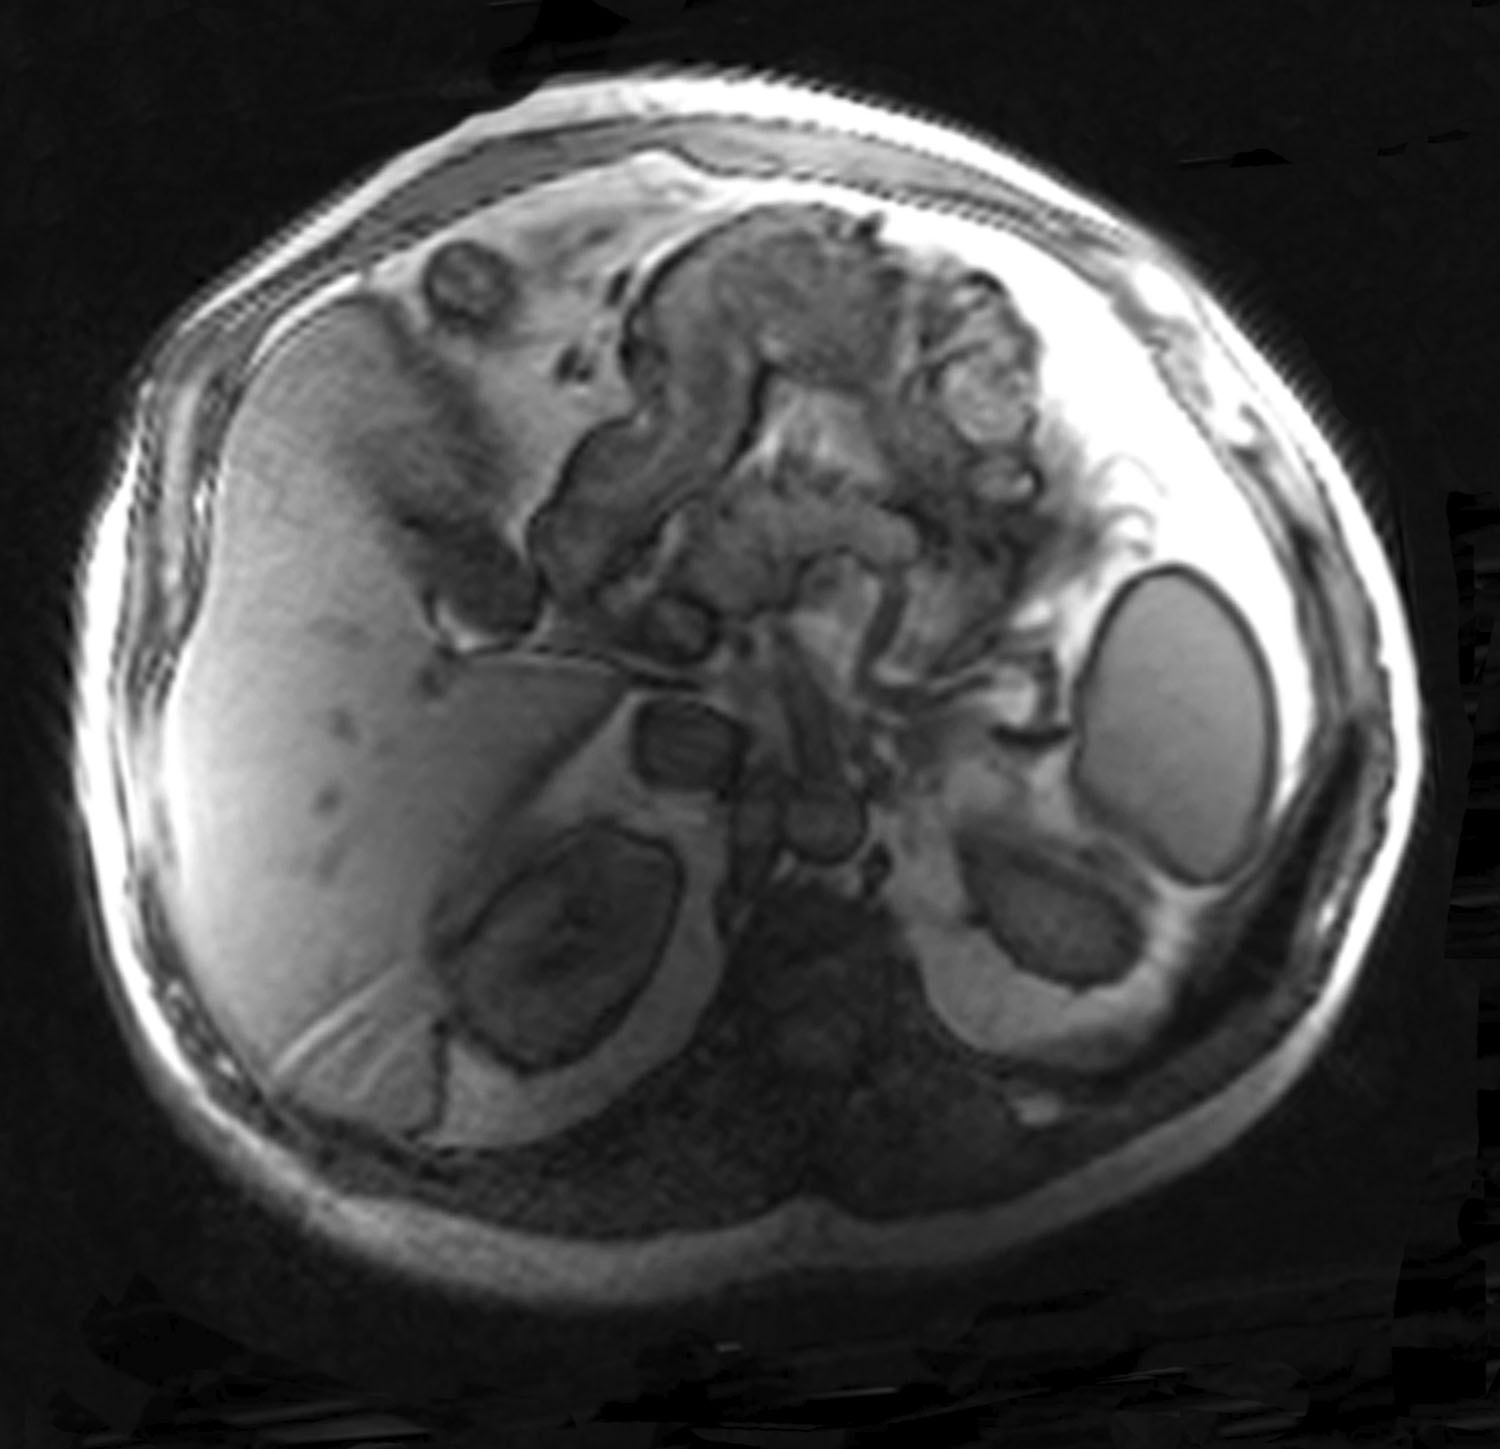

Figure 24. Case 2: Magnetic resonance imaging taken in left lateral decubitus. Note the dysmorphic protuberant anterior abdominal wall preoperatively.

Figure 25. Case 2: Magnetic resonance imaging view shows the improved abdominal wall shape postoperatively along with the hypertrophied abdominal wall musculature.

Furthermore, we have noted hypertrophy of the abdominal wall musculature after tightening, as is supported in postoperative magnetic resonance imaging scans, which have demonstrated hypertrophied muscle along with an improved overall abdominal wall shape because of globally restored muscular tension. In parallel, Hicks et al noted muscular hypertrophy after the creation of a new linea alba following abdominal component separation.20 We theorize that this phenomenon is likely due to repositioning the muscle in a better position on the force/length curve, as discussed above.